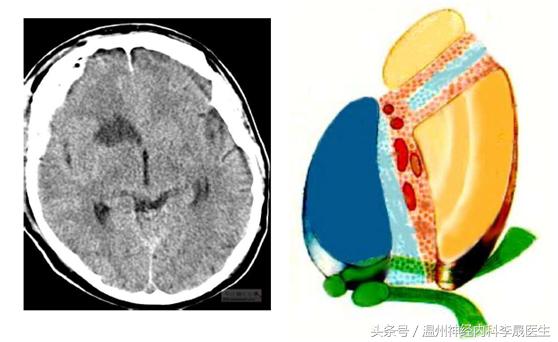

(一)大脑前动脉在前交通与Heubner返动脉之间闭塞

1)对侧上神经元性瘫痪,下肢重,上肢轻。

2)对侧下肢感觉障碍

3)额性共济失调

4)精神症状:如缄默、运动减少等。